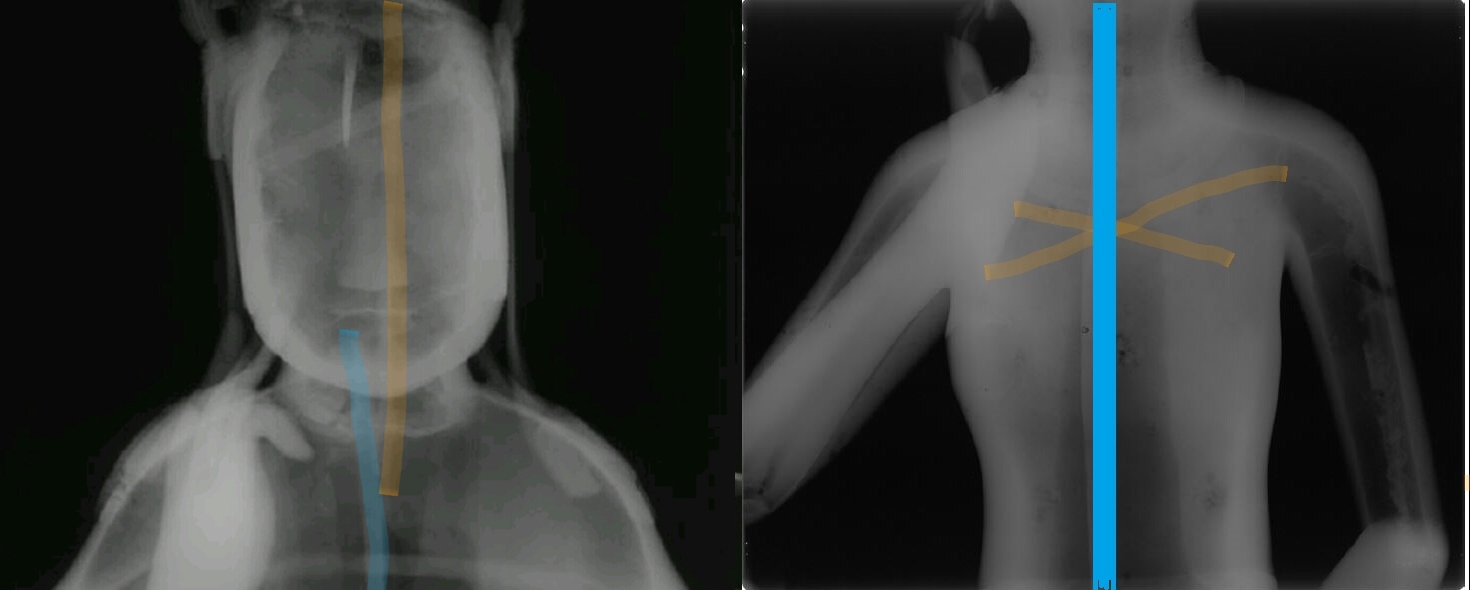

감마선 촬영 결과 78호의 경우 등 부위, 즉 목걸이와 늘어진 U자형 천의(보살 등이 입는 얇은 옷) 사이에 반타원형 동판을 따로 붙인 흔적을 확인했다. 주조할 때 생긴 구멍을 동판으로 붙여 수리한 흔적이었다. 지금까지 육안으로 관찰되지 않았던 수리흔적이 첨단과학을 동원하고 나서야 겨우 드러난 것이다.

그런데 78호를 감마선으로 분석해봤더니 철심틀이 분리되어 있었다.

이것은 점토(내형토)로 맨처음 형상을 만들 때 몸체와 머리 부분을 각각 따로 만들어 붙였다는 뜻이다. 왼발의 연화좌(불상이 앉는 자리) 역시 따로 제작해서 붙였다.

이렇게 별도로 만들어 붙였기 때문에 미세한 균열이 생겼고, 그 사이에 청동 쇳물이 흘러들어가 거스러미(까칠까칠한 부분)이 생겼다. 하지만 이 또한 육안이나 X선 촬영으로는 잡아낼 수 없는 흠결이었다.